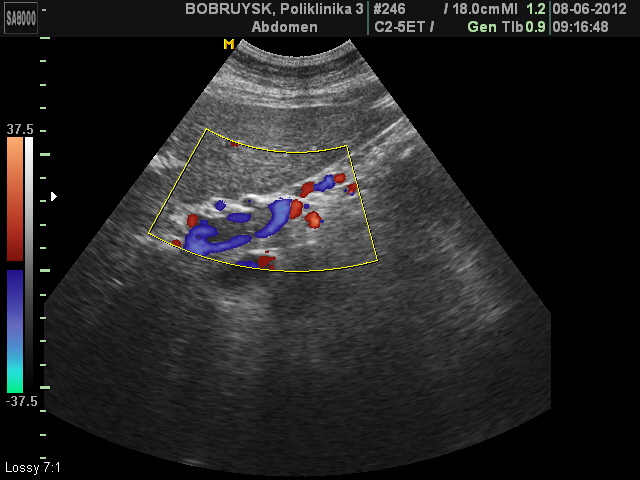

Женщина 62 лет.

Неполный тромбоз воротной вены и ее ветвей

У нас в хирургической клинике пилетромбоз чаще всего случается на фоне панкреатитов. Особенностью этих тромбозов является их слабая регрессия; чаще всего они не реканализируются, а кровоток частично восстанавливается через венозные коллатерали.

Причин данного тромбоза не знаю, т.к пациентка пришла только с предыдущим УЗИ и результатами ангиографии с Минска.

Сослов пациентки, проходит амбулаторное лечение тромболитиками, рекомендовано УЗИ в динамике, по месту жительства и консультации по графику в Минске.